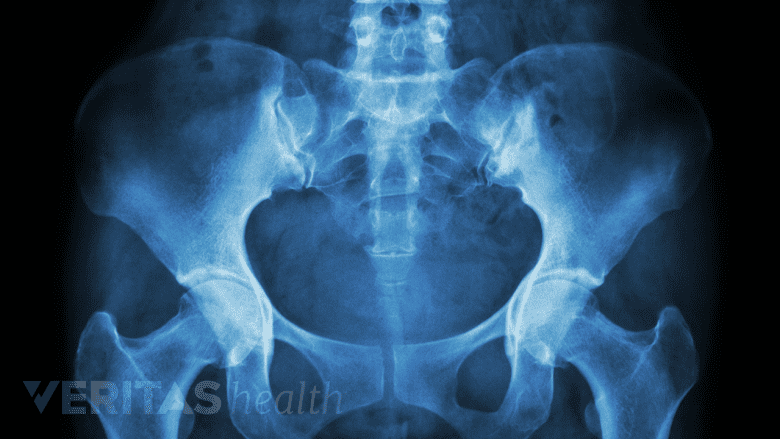

The sacroiliac joint connects the hip bones to the sacrum, primarily acting as a shock absorber.

The sacroiliac joint is a low-motion joint that connects the hip bones to either side of the sacrum, acting primarily as a shock-absorber between the lower body and torso. This joint can also be thought of as the point where the base of the spine connects to the pelvis. The sacroiliac joint is a combination of a synovial joint and the sacroiliac ligaments.

X-rays are helpful in diagnosing sacroiliac joint dysfunction.

- Diagnostic imaging tests, including an x-ray, CT, or MRI scan, are mostly used to rule out other possible causes of low back pain. Sacroiliac joint dysfunction does not usually show up well on an imaging test the same way a herniated disc, bone spur, or arthritic joint might. For this reason, an imaging test may not be used at all to diagnose SI joint pain.